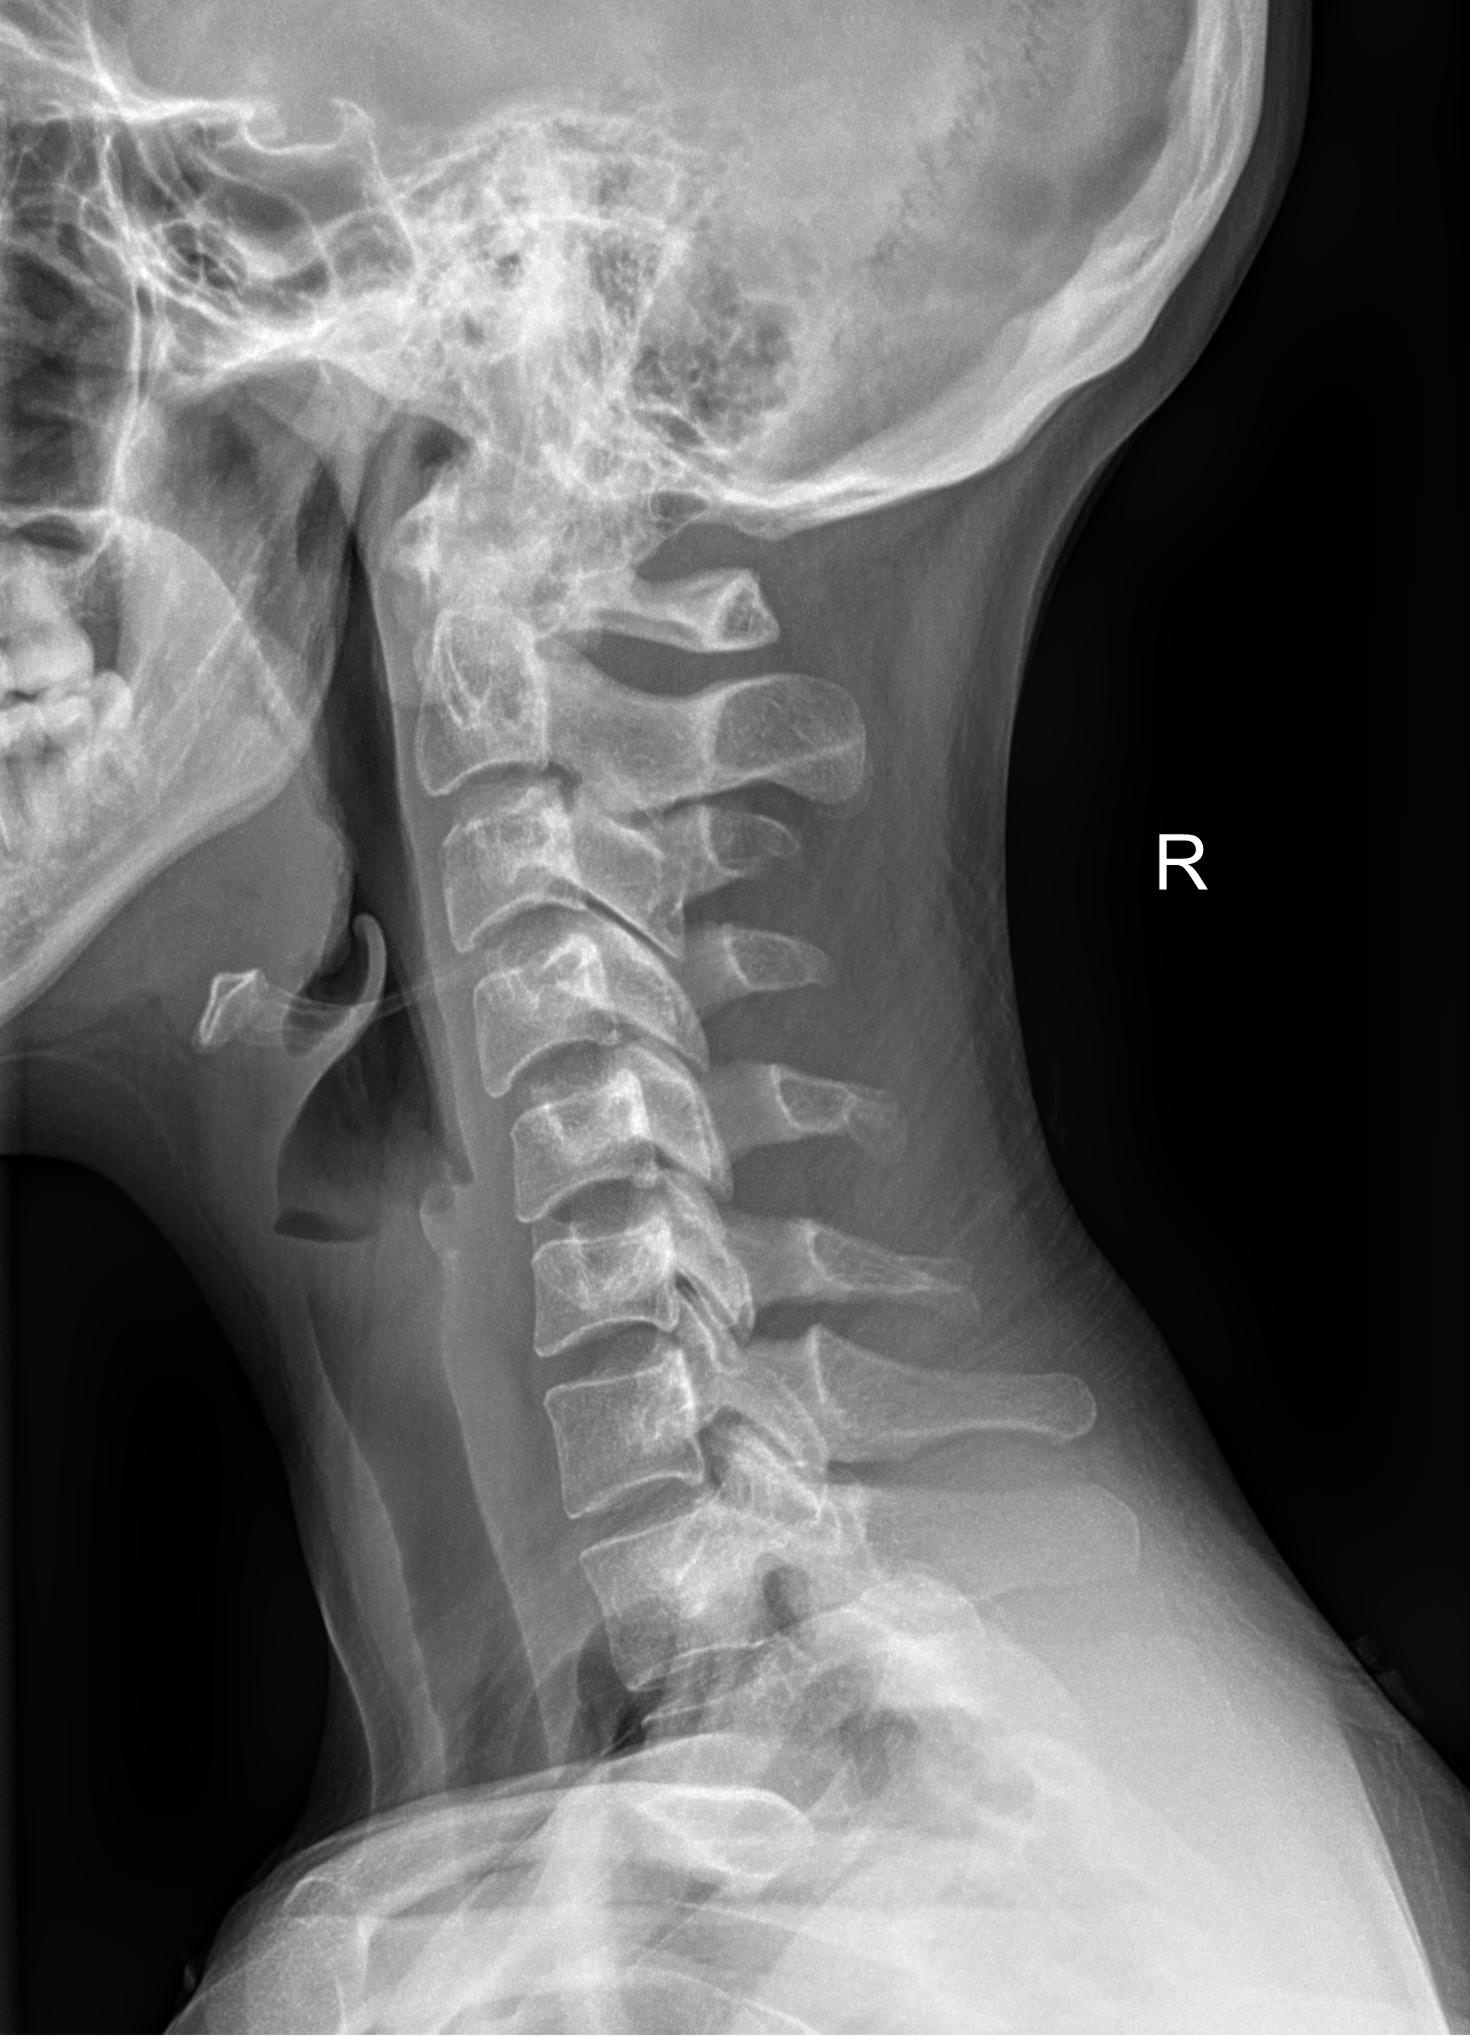

В качестве подготовки необходимо снять все металлические украшения с шеи и головы, расстегнуть пуговицы и надеть защитную накидку. Диагностика выполняется в положении стоя или сидя, всего делается 3 снимка:

• В боковой проекции ― строго боком к детекторной пластине;

• В условиях максимального разгибания головы назад;

• В положении максимального наклона головы вперед.